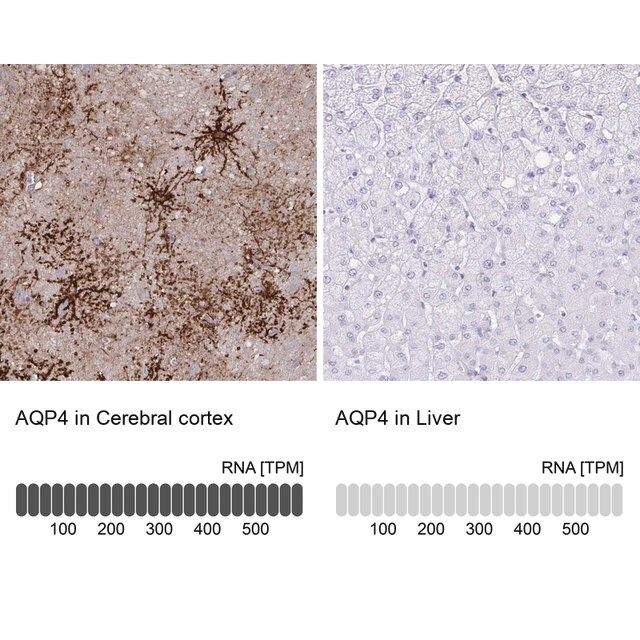

水通道蛋白 4 (aquaporin 4,AQP4) 是一种内源性蛋白,属于水通道蛋白家族,由 13 个成员组成。该基因位于人类 18 号染色体 q11-q12,有 4 个外显子和 3 个内含子。编码的蛋白有 5 个环,由 6 个跨膜结构域干预。环 A、C 和 E 面向浆外区,环 B 和 D 存在于胞浆区。在肺、胃和肾等外周器官中表达。是中枢神经系统表达的主要水通道。它由星形胶质细胞表达,并优先定位于星形胶质细胞的终足突起。它以两种可变剪接形式存在— 长的称为 M1,短的称为 M23。

人类蛋白质图谱项目可细分为三个方面的工作:人类组织图谱、癌症图谱和人类细胞图谱。支持 Tissue and Cancer Atlas 项目而产生的抗体,已经通过免疫组化针对数百个正常和疾病组织进行了测试,通过 Human Cell Atlas 项目最近的努力,很多已经通过免疫荧光法进行了表征,不仅在组织级别,现在也在亚细胞级别绘制了人类蛋白质组图谱。通过点击图像库链接,可以在 Human Protein Atlas (HPA) 位点上查看这些图像和这个庞大数据集的集合。要查看这些协议 和其他有关 Prestige 抗体和 HPA 的有用信息,请访问sigma.com/prestige。

水通道蛋白 4 (aquaporin 4,AQP4) 是脑内主要的水转运体,被认为是维持脑内水分稳态的重要物质。因此,AQP4 可能在脑水肿的发病机制中起重要角色。研究显示,这种转运体在脑缺血中过度表达。因此,它可能有潜力成为缺血性脑水肿的治疗靶点。该基因多态性与脑损伤反应和脑外伤患者的临床预后相关。AQP4 的短亚型 (M23) 有利于颗粒正交排列 (orthogonal array of particles,OAP) 的形成,OAP 的大小由短 (M23):长 (M1) 亚型的比例决定。已知这些 OAP 与视神经脊髓炎 (NMO) 中产生的致病性自身抗体相互作用。因此,对该蛋白的进一步研究可能为 NMO 的发病机制和治疗提供见解。

- 44例正常人类组织以及20例最常见癌症类型组织的IHC组织阵列。

| 增强验证 | orthogonal RNAseq Learn more about Antibody Enhanced Validation |